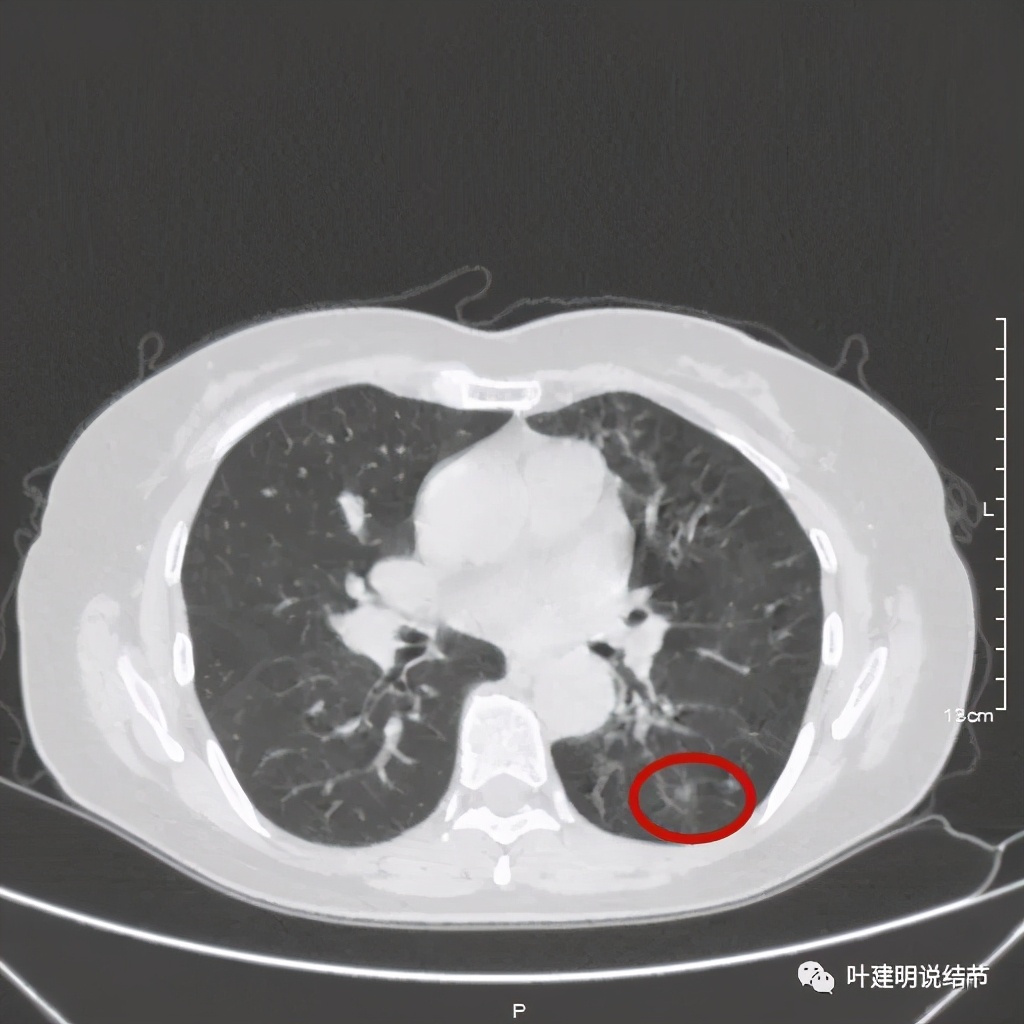

其实若从以上影像上看,恶性还真不能除外的,相对来说,恶性的可能应该大于良性。但看肺结节,我们在看细节特征的同时,还要看其他肺野有没有异常,综合来考虑。因为她的左下肺其他部位有病变存在,先来看下图像:

左下肺野多发支气管扩张呈囊状,也有一些实性密度的结节(考虑扩张支气管内的痰栓)。右侧也有实性炎性病灶。所以综合来看,左下之前的结节也得考虑与这些同源,一个原因来解释更为合理,所以恶性的可能性又小了。我建议其随访观察。昨天来复查,我们来看下这次的CT图像: